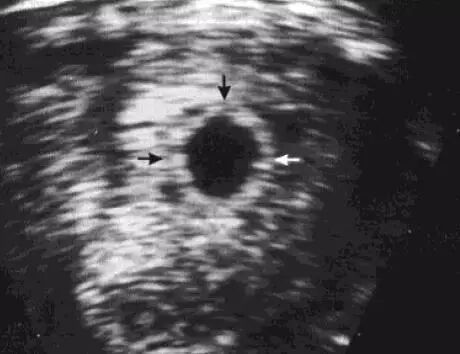

卵黄囊是卵子受精2周后滋养层内壁细胞迅速分裂、分化形成的一个囊腔,也是妊娠囊内超声可见的首个解剖结构。超声表现为亮回声环状结构,中间为无回声区,位于妊娠囊内,大小3~8mm。经腹超声最早6周可查见,经阴道超声最早5周查见,约10周时消失,12周后完全消失。

卵黄囊是确定宫内妊娠的标志,它的出现可以排除宫外妊娠时宫内的假妊娠囊。妊娠囊>20mm而未见卵黄囊或胎儿,可能是胚胎坏死。

妊娠8周,卵黄囊呈一高回声环状结构位于妊娠囊内